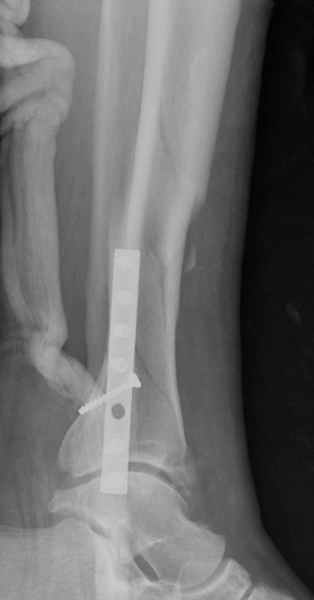

спрашивает что делать с больным который поступил недавно, фермер 55 лет падение при пьяной драке в баре, года два назад перенес операцию на лодыжке, на снимках и КТ перелом без вовлечения сустава,

Повреждение такой локализации, на которой применимы и аппарат (классический Илизарова или гибридный), пластина, особенно Locked Plate, и гвоздь с блокированием. В нашей клинике был бы выполнен закрытый интрамедуллярный остеосинтез. Желательно использовать гвоздь с возможностью провести более чем 2 обычных фронтальных винта в дистальном отломке.

Здесь мы использовали новый Synthes Nail с дополнительными дырками, в проксимальной части 4: по две косых и поперечные (один стандартный а другой динамический), в дистальной части две поперечные, прямая и косая. Вес больного более 120 кг, нагрузку начнем через месяц.

Получилось красиво, поздравляю. Вверху можно было ограничиться одним винтом во фронтальное статическое отверстие, зачем два 45-градусных?

При такий спирали задний край tibia может быть сломан - нет ли этого в данном случае? На всякий случай можно было ввести 1-2 винта 4,5 мм спереди назад мимо гвоздя. Хотя самый дистальный блокирующий винт, возможно, зацепил этот отломок. А какой тут диаметр гвоздя и locking винтов?